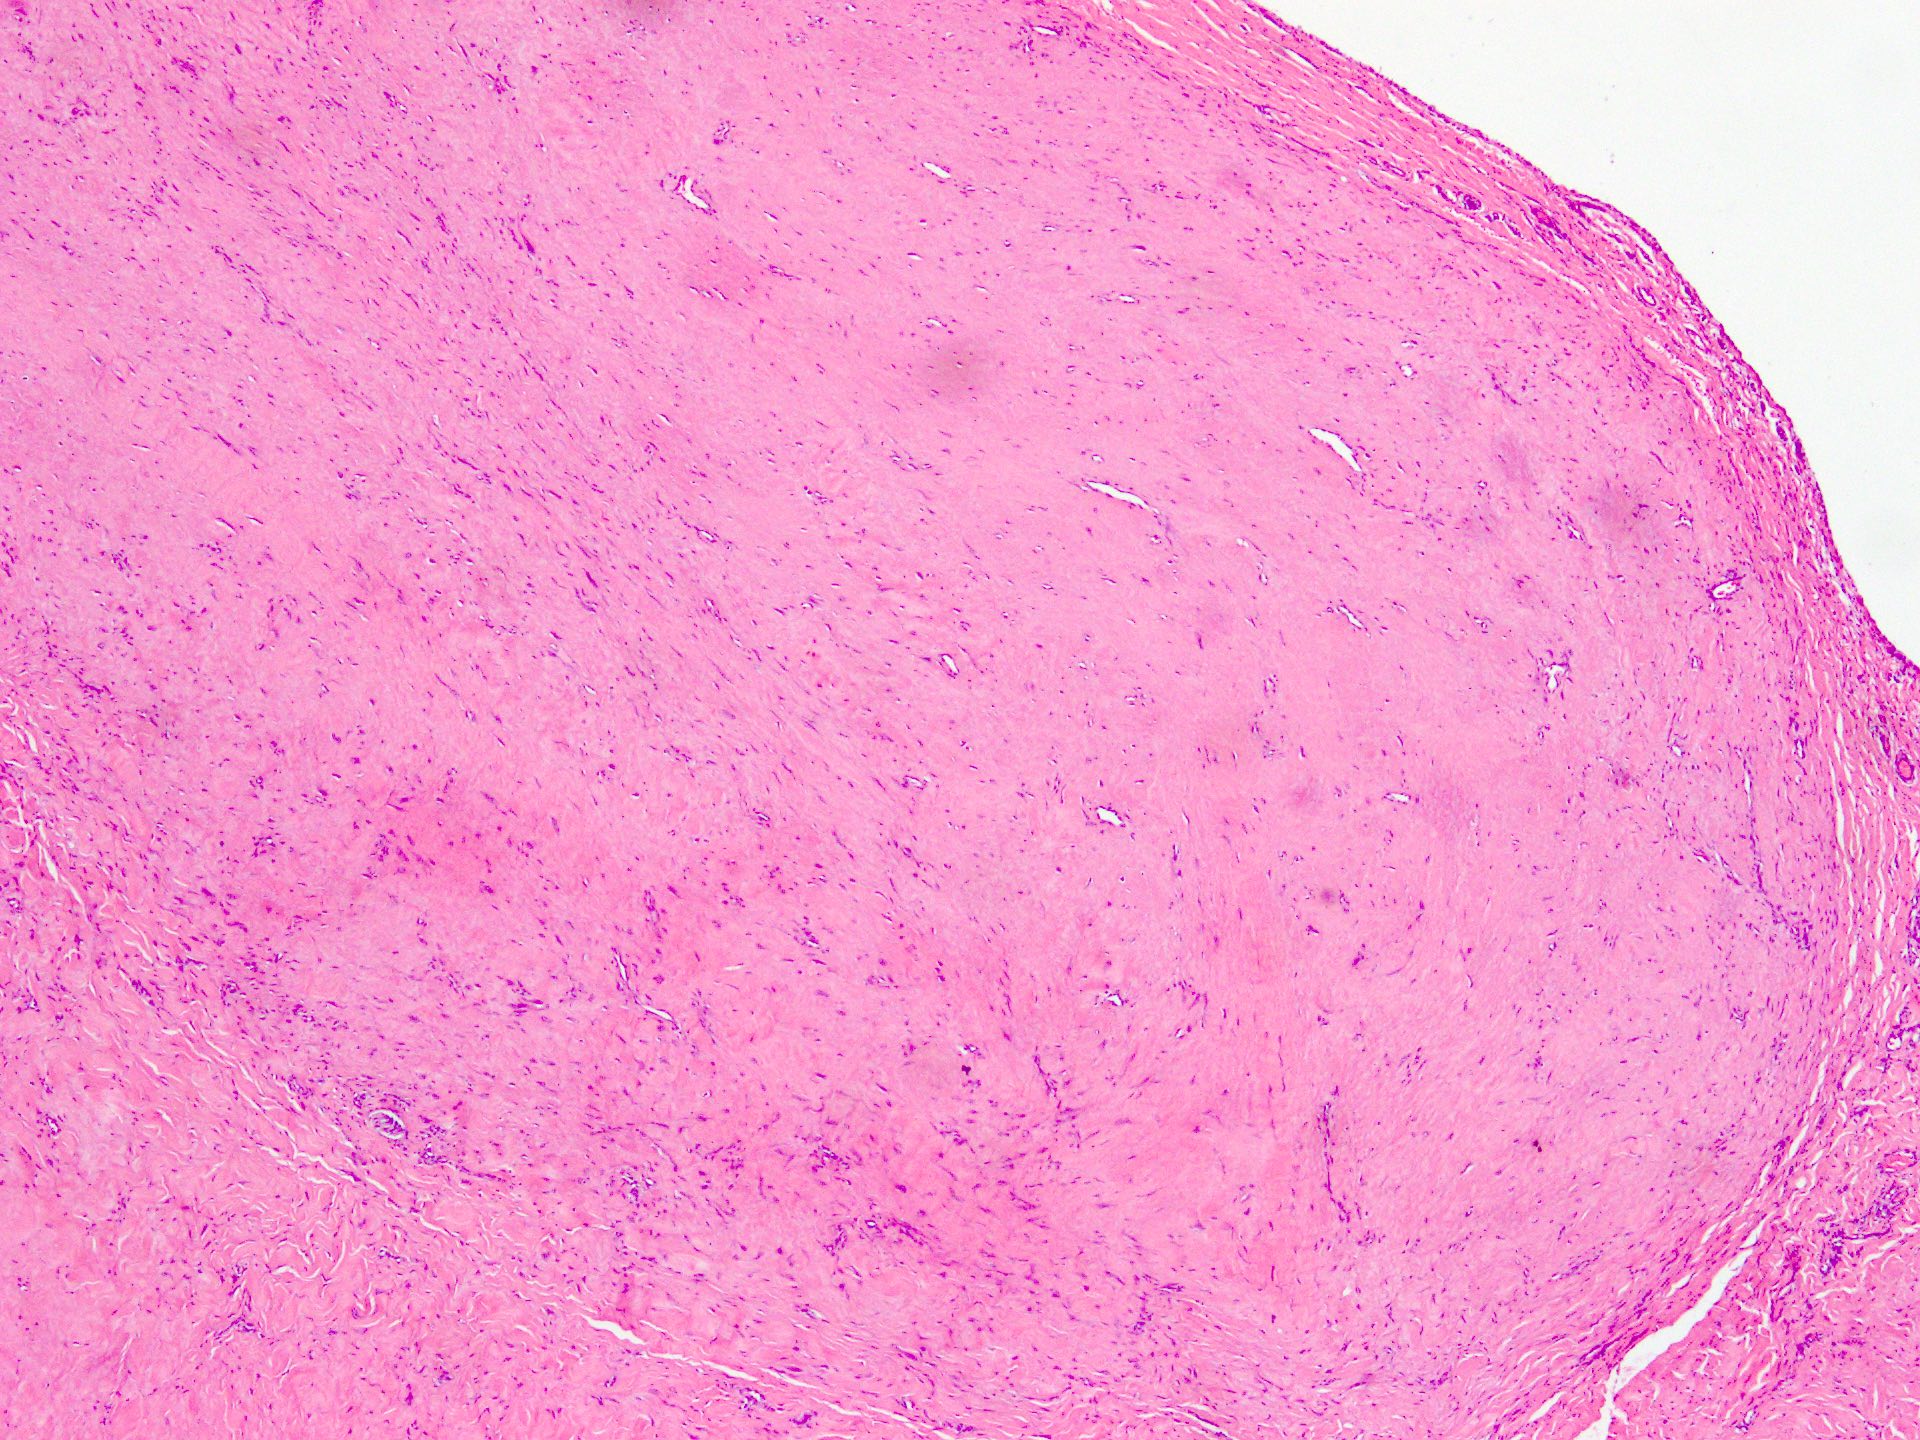

Microscopic (histologic) description

- Well circumscribed tumor of variable cellularity

- Cellularity mostly higher at tumor edges

- Bland spindle cells in a collagenous background

- Tumor has characteristic thin walled slit-like vessels

- Degenerative changes like myxoid / cystic change, osseous / chondroid metaplasia can be seen

- Bizarre pleomorphic cells can also be present

- Mitotically inactive

- Necrosis not present

- Cellular variant of fibroma of tendon sheath also exists; it overlaps morphologically with nodular fasciitis and fibrous histiocytoma (Cancer 1979;44:1945)

Microscopic (histologic) images

Contributed by Nasir Ud Din, M.B.B.S.

- Comment: Histology showed a well circumscribed, variably cellular lesion composed of bland spindle cells having regular nuclei arranged in sheets and fascicles. Thin walled vessels are present. The background is collagenous.

A 32 year old man has had painless swelling in the palm of his hand for 6 months. It was excised and the histology is shown in the above image. What is the most likely diagnosis?